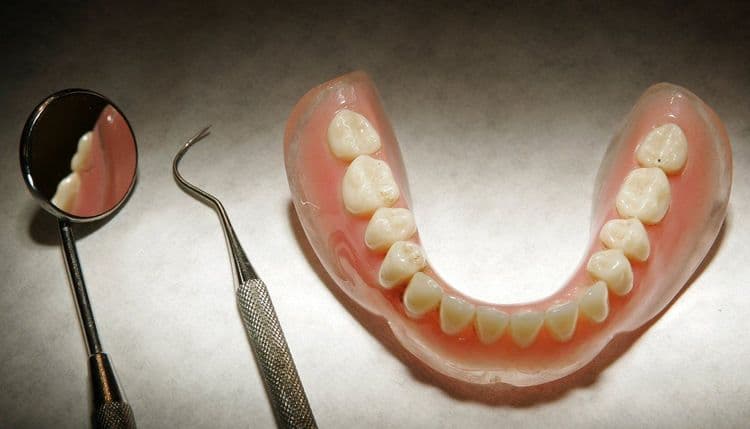

ऑपरेशन होतं पोटाचं आणि दात अडकले घशात असा विचित्र प्रकार आहे हा !!

सरळ मुद्द्याला हात घालूया. त्याचं झालं असं, की युकेच्या एका ७२ वर्षांच्या आजोबांवर पोटाची शस्त्रक्रिया करण्यात आली होती. शस्त्रक्रियेच्या ६ दिवसानंतर हे आजोबा पुन्हा हॉस्पिटलमध्ये आले, तेव्हा त्यांच्या घशातून रक्त निघत होतं. त्यांचा घसा दुखत होता, अन्न गिळता येत नव्हतं आणि खोकल्यासोबत रक्त येत होतं. त्यांनी डॉक्टरांना म्हटलं की ऑपरेशन झाल्यापासून त्यांना अन्न गिळता येत नाहीय.